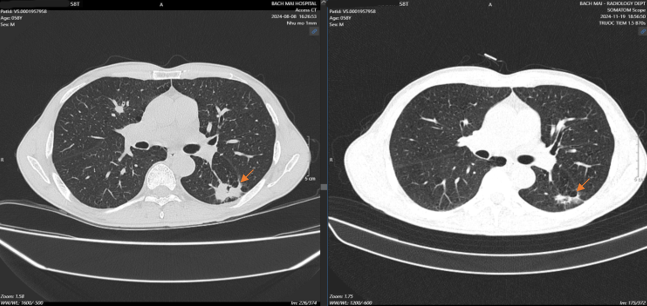

CT ngực có tiêm thuốc: Khối tỷ trọng tổ chức thùy dưới phổi trái , 21x29x19mm, bờ tua gai, ngấm thuốc mạch và không đồng nhất sau tiêm, cắt cụt nhánh phế quản gần kề. Giãn phế nang lan tỏa hai bên trường phổi, ưu thế thùy trên. Hạch trung thất nhóm 2L, 4L, lớn nhất kích thước 12x23mm, ngấm thuốc kém và không đồng nhất sau tiêm.

Theo dõi đáp ứng trên hình ảnh học (chụp CT ngực)

Sau 4 chu kỳ điều trị, tổn thương phổi giảm kích thước, nhu mô thùy dưới phổi trái còn đám tổn thương 23x19mm.